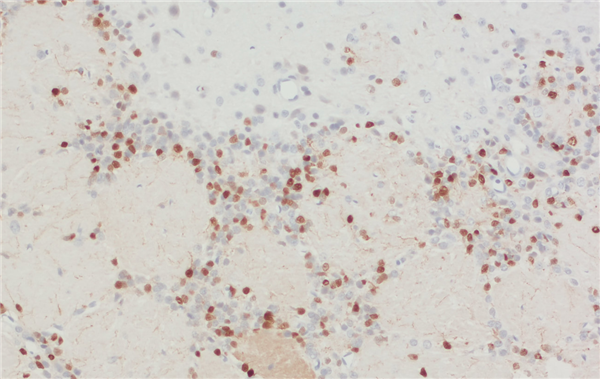

示例:采用雞抗 Calretinin 抗體(產(chǎn)品編號 214 109,稀釋度 1:200,DAB 染色,棕色)對甲醛固定的石蠟包埋(FFPE)大鼠腦切片進行間接免疫染色。細胞核通過蘇木精染色顯示為藍色。